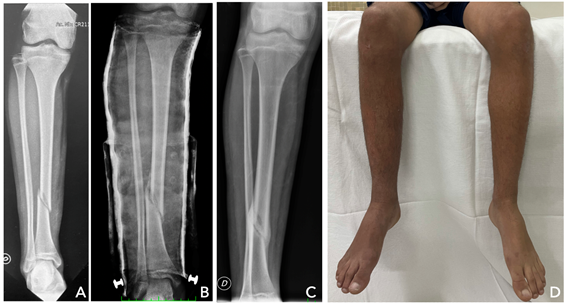

Tuvimos 2 pacientes que presentaron complicaciones menores, a los cuales se les rompió la cazoleta abisagrada plástica a la tercera semana del tratamiento funcional. Destacamos que en uno de los casos la misma se rompió mientras el paciente practicaba fútbol con su yeso funcional. Como ya mencionamos, un paciente presentó una angulación mayor a 5º (6º de varo) Figura 4, la misma era imperceptible clínicamente. Por lo que estamos ante una técnica segura con bajo o nulo número de complicaciones, la cual nos permite en caso de que sea necesario cambiar de tratamiento según lo requiera la situación de la lesión y el paciente. Evitando complicaciones inherentes a tratamientos quirúrgicos como son lesiones nerviosas o fisarias iatrogénicas, infección relacionada a materiales de fijación, intolerancia de implantes, entre otras 1

Figura 4: A) Radiografía inicial de fractura tercio distal de tibia sin desplazamiento, peroné sano. B) 4 semanas de período funcional, se observa desplazamiento en varo del foco fracturario. C) Fractura consolidada con 6º de varo. D) Situación clínica al momento de consolidación, no repercusión morfológica ni funcional de pierna.